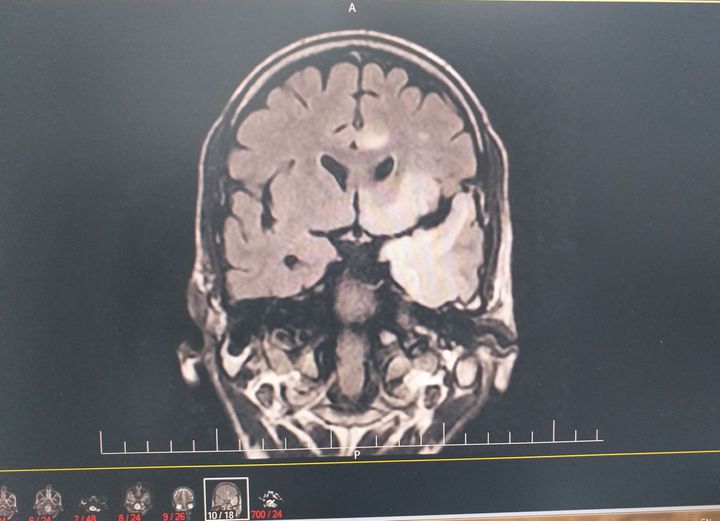

What is your diagnosis?

HSV encephalitis